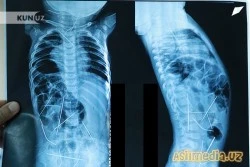

Рентген суратларида аён бўлдики, чақалоқнинг танасида 16 дона (!) игна бор ва улар энг камида икки ойдан буён болани қийнаб келади. Шундай қилиб, бола ва унинг онаси зудлик билан Тошкентга юборилди. Республика шошилинч тиббий ёрдам илмий марказига келтирилган бола тезкорлик билан жарроҳлик столига ётқизилди.

Марказдаги Болалар жарроҳлик бўлими мудири, профессор Акиловнинг таъкидлашича, барча игналар танада турлича жойлашган: уларни чақалоқнинг йўғон ичак қисмида, сийдик қопи, кўкрак қафасида, боланинг бўйин қисмида, умуртқа поғонасида, юрак остида аниқлашган.

«Орқа умуртқа суягига тегиб турибди, қаранг, буни қандай изоҳлаш мумкин? Бола майда конструктор, батарейкани ютиб юборишини кўп кузатдим, аммо игналар тилиб ташлайди. Ваҳоланки, у фақат саккиз ойлик болакайку», дейди профессор.